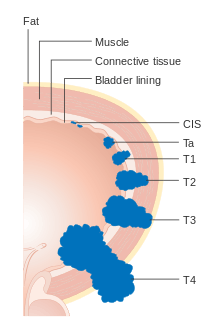

Staging

The TNM staging system for bladder cancer is as follows:[23]

T (Primary tumour)

- TX Primary tumour cannot be assessed

- T0 No evidence of primary tumour

- Ta Non-invasive papillary carcinoma

- Tis Carcinoma in situ ('flat tumour')

- T1 Tumour invades subepithelial connective tissue

- T2a Tumour invades superficial muscle (inner half)

- T2b Tumour invades deep muscle (outer half)

- T3 Tumour invades perivesical tissue:

- T3a Microscopically

- T3b Macroscopically (extravesical mass)

- T4a Tumour invades prostate, uterus or vagina

- T4b Tumour invades pelvic wall or abdominal wall

The treatment of bladder cancer depends on how deep the tumor invades into the bladder wall.